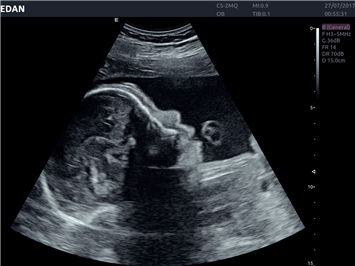

EDAN Acclarix LX4 представляет собой инновационную ультразвуковую систему, построенную на усовершенствованной платформе Acclarix. Сочетание высокого качества визуализации с интеллектуальным рабочим процессом делает эту систему оптимальным выбором для клиник, ценящих эффективность и экономичность.

• 3D/4D-визуализация с автоматическим редактированием объема (eFace)

• Автоматизированные измерения в акушерстве

Области применения:

Система Acclarix LX4 оптимально подходит для:

• Акушерства и гинекологии

3D/4D:

Да